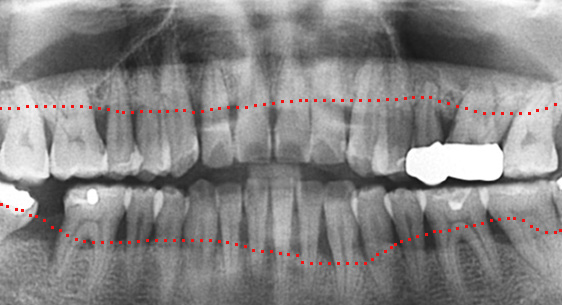

심한 염증으로 치조골이 광범위하게 소실, 아래쪽 신경관이 가까이 있어 치근단수술이 불가능한 상태, 타 병원에서 임플란트 진단을 받았지만, 고운미소치과에서 치아를 발치하고 뿌리 쪽 염증을 제거한 후 발치한 치아를 다시 심는 치아재식술을 시행하였습니다.

기존 신경치료 부위에 염증과 치조골이 소실되고 있는 상태

치아를 발치하고 염증을 제거, MTA로 충전하고 치아를 다시 심음.

(난이도 최상)